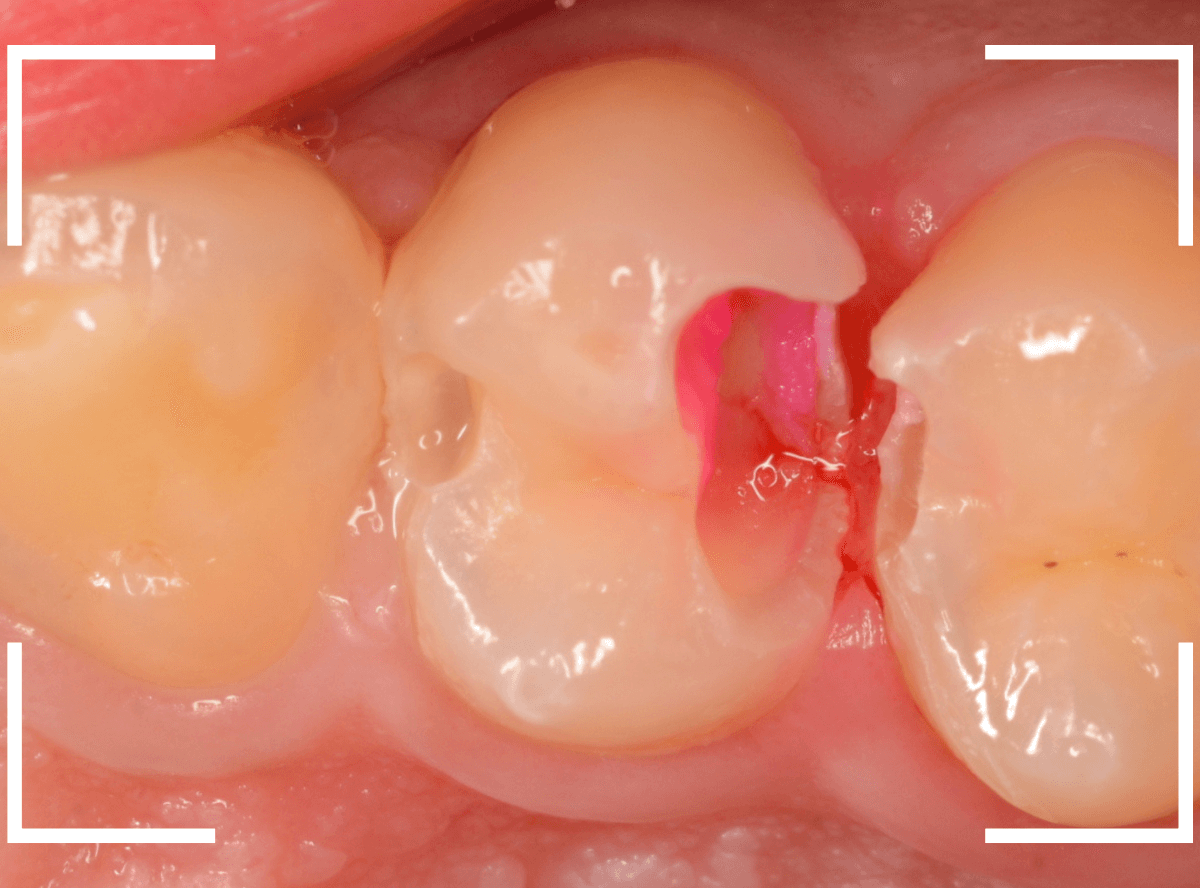

Case.23 歯のすきまから両側が大きな虫歯

「下の奥歯が痛む」という訴えで来院された患者さんのケースです。

目視でも、手前の奥歯がかけていて、中で虫歯が広がってるであろうことは予想できます。

状況から、まず手前の奥歯から治療となりました。

麻酔をして、手前の奥歯のレジンを慎重に外します。

前に虫歯の治療をした時点で、神経スレスレの状態でしたので、削りすぎないように慎重にレジンを外さなければいけません。

レジンを外して、う蝕検知液で確認します。

レジンの中で虫歯が進行していたのがわかります。

慎重に全ての虫歯を除去しました。

何とか、神経が露出せずに済んでいます。

お薬をつめて、セメントで蓋をして経過観察します。